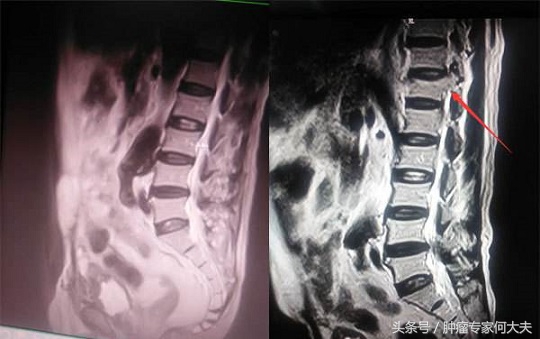

骨转移

2015年9月患者腿疼、腰疼,全身骨扫描提示右侧股骨、腰椎、胸骨等多发骨转移,进一步相应部位的核磁检查提示骨质破坏严重,此时再继续服用克唑替尼的基础上,每月增加一次唑来膦酸抗骨转移治疗。间断服用泰勒宁等镇痛药物患者疼痛控制尚满意,但是老太太骨转移后生活质量明显下降,此后的生活基本上已卧床为主。但食欲一切都好。